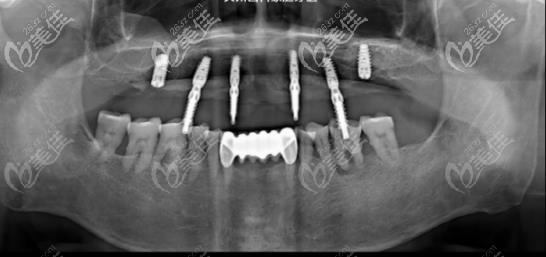

在家人的陪伴下来到了曲江大川口腔,到院后表示就想能正常吃个饭,院内医生在经过检查后定出方案:拔除剩余三颗残冠,进行半口种植修复,通过植入6颗植体,再带上连桥冠修复。

说到这,可能就有朋友不懂为什么上颌缺了14颗牙齿,为什么只植入6颗植体,不全部种呢!其实半口牙齿缺失并不一定要采用传统的点种模式去种牙。

传统点种模式不仅费用高,而且顾客所承受的痛苦也会增加,恢复期慢等等,而植入六颗植体,再带上连桥冠,这样不仅花费少、恢复时间还快,属于更为先进的种牙技术。